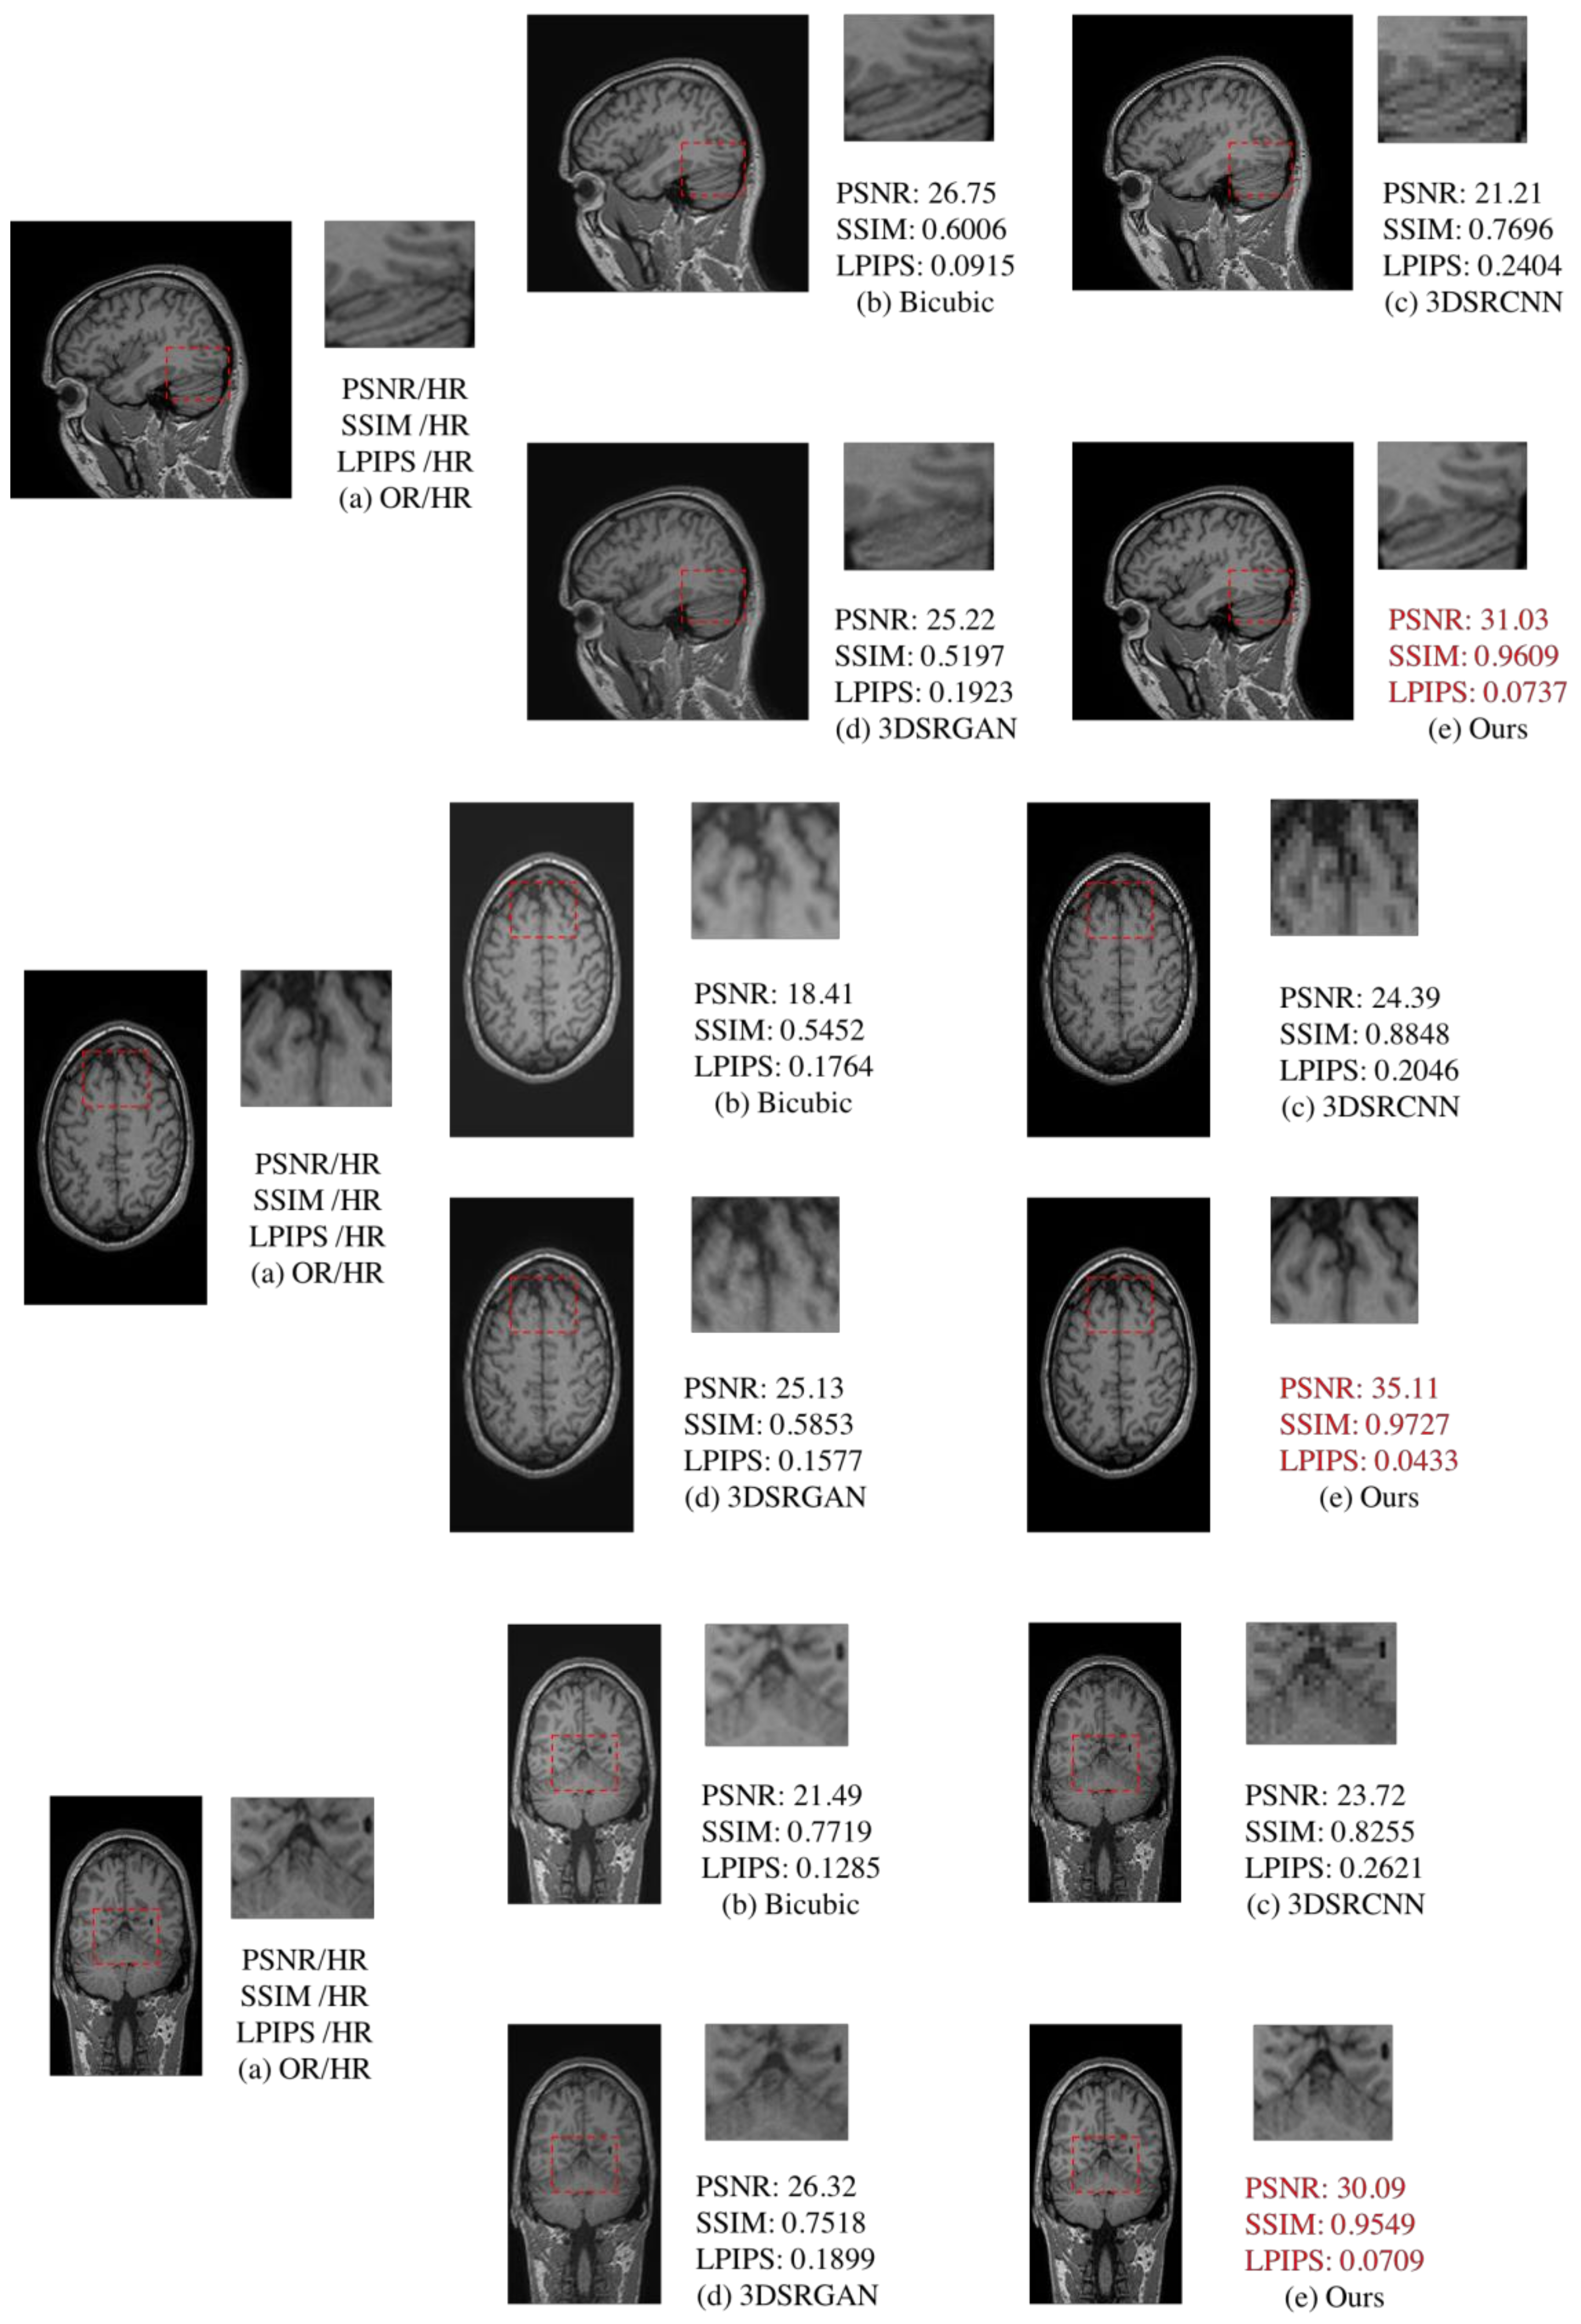

4.3. Comparison of 2D and 3D

Three-dimensional reconstruction of MRI images can usually be carried out with a three-dimensional convolutional neural network [22,23,24]. We also compared traditional 3D MRI super-resolution reconstruction methods [22,23] (Table 3). Compared with 3DSRCNN and 3DSRGAN, our approach maintains advantages in image evaluation and detail comparison (Figure 13).

Figure 13.

Comparison of 3DSRCNN [21], 3DSRGAN [22], bicubic, and proposed method. (a) is the original high-resolution MRI slice. (b) is new slice after interpolation of bicubic. (c,d) are 3D super-resolution methods in deep learning. From this comparison, (e) is our proposed method which includes two super resolution reconstruction steps (RFB-ESRGAN and nESRGAN). (e) performs better than (c,d) in the scope of high-frequent information and visual quality. Besides, (e) also get better performance in the image quality evaluation.